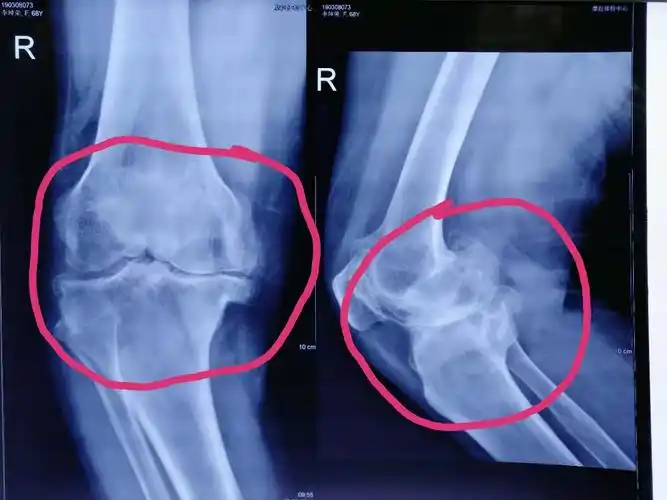

【科普】长骨刺是钙太多了了吗?

骨刺是骨骼上的异常骨增生,常常发生在关节或骨头结合处,可能导致疼痛

骨刺是骨头表面突出的一块硬物,实际上叫刺不准确,大部分骨刺都是圆形